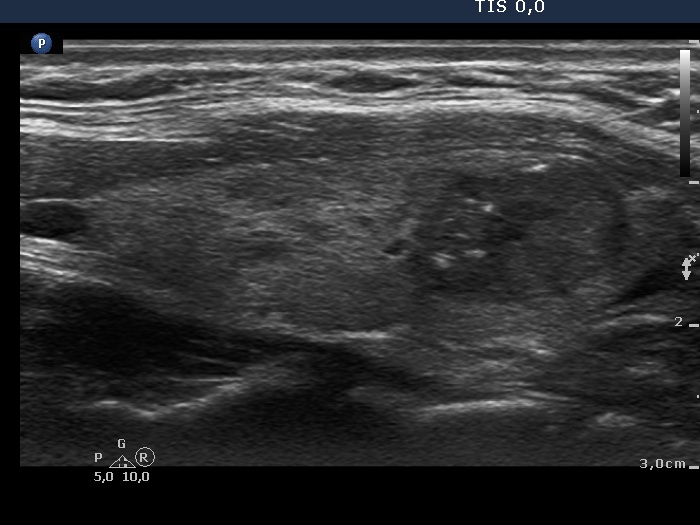

Right lobe, longitudinal scan

Left lobe, another longitudinal view. The borders are lobulated.